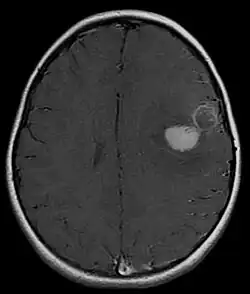

The approach to management of a CNS PNET is first to obtain detailed imaging through MRI, as well as additional scans of the patient's body (X-ray, CT, PET, even bone marrow biopsies) to look for metastasis or other associated malignancies. The tumor will then need to be biopsied to confirm the diagnosis. After the diagnosis of a CNS PNET is confirmed, management includes neoadjuvant chemotherapy and radiation (to reduce tumor size burden), complete surgical resection with confirmed negative margins, and/or additional adjuvant post-surgical chemotherapy. CNS PNET is aggressive and must be managed as so. Palliative care services should also become involved in the patient's care team when the diagnosis is made. [6]